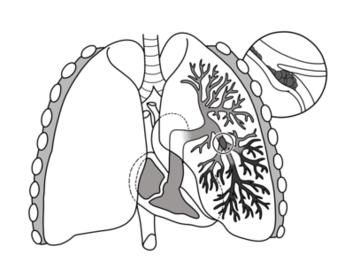

Pulmonary embolism

Pulmonary embolism is a blockage of an artery in the lungs by a substance that has moved from elsewhere in the body through the bloodstream. Symptoms of a PE... Wikipedia